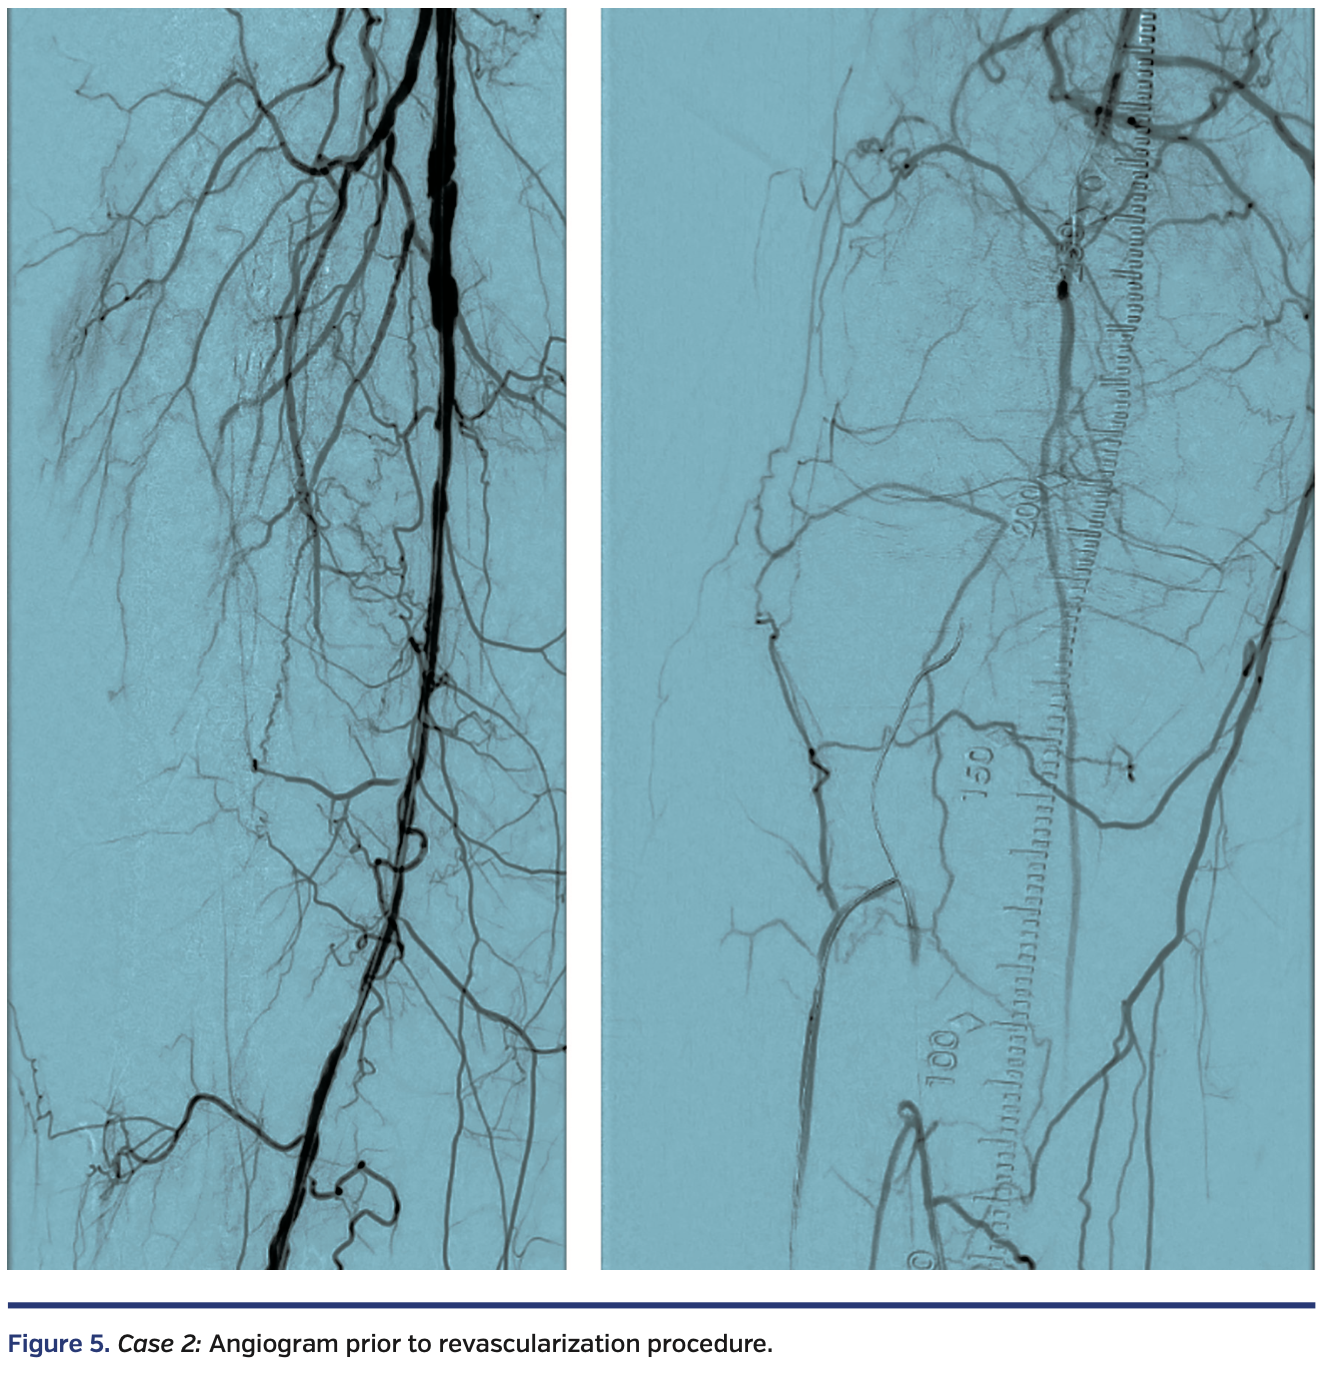

A functional white female in her late eighties with history of type 2 diabetes, hypertension, and hyperlipidemia presented with progressive right hallux discoloration and early pre-gangrenous changes over a 2-month period. Arterial duplex suggested a right popliteal artery (P3 segment) occlusion, distal posterior tibial artery occlusion, and patent anterior tibial and peroneal arteries. Diagnostic angiography, performed through antegrade access into the right common femoral artery, revealed a diffusely diseased right superficial femoral artery (SFA) and occluded P2 and P3 segment popliteal artery, with 3-vessel tibial vessel reconstitution by collaterals (Figure 5).